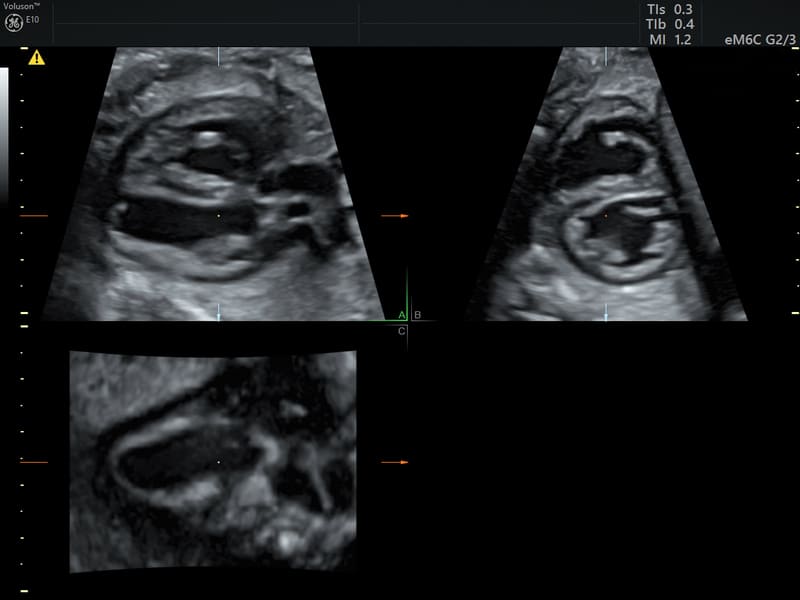

Nuova sonda convex volumetrica a matrice elettronica eM6C G3: questo trasduttore si distingue dalle sonde tradizionali per l’assenza di parti meccaniche in movimento: utilizzando lo steering elettronico di oltre 8000 elementi in matrice convessa consente di eseguire acquisizioni ultraveloci mantenendo una qualità d’immagine eccezionale e, grazie alla modalità “biplane”, permette la visualizzazione in tempo reale di due piani ortogonali in real time, migliorando il workflow e la riproducibilità dell’acquisizione

SonoCNS: tool semiautomatico per allineare e visualizzare correttamente le scansioni consigliate nei piani TV (trans-ventricolare), TT (trans-talamico), TC (trans-cerebellare), unitamente alle misurazioni del cervello fetale, utilizzando la tecnologia di deep learning GE Healthcare partendo da un’unica acquisizione 3D.